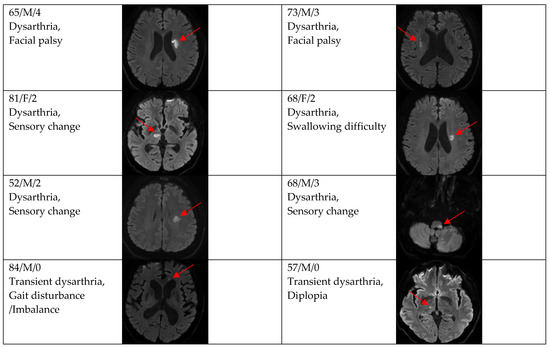

3. Results